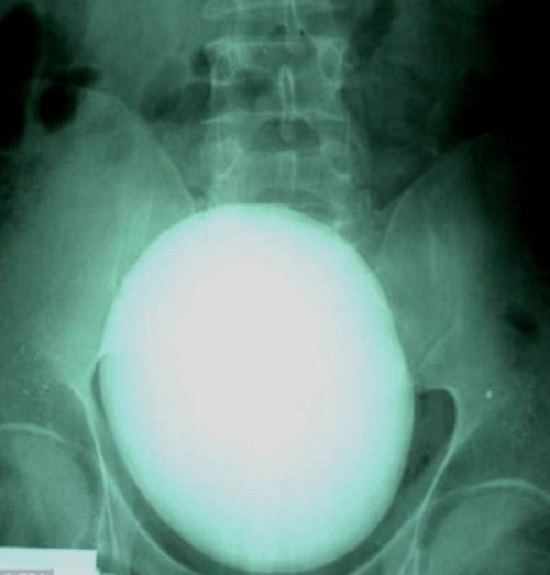

Камни в почках: снимок 15-сантиметрового конкремента

Камни в почках являются результатом достаточно сложных физико-химических процессов, вкратце суть их появления можно определить так, что в их основе лежит постепенная кристаллизация солей в составе мочи и последующее их осаждение. Размеры камней в почках могут быть самые различные, начиная от нескольких миллиметров, что определяет их как песок в почках, до десятка сантиметров.